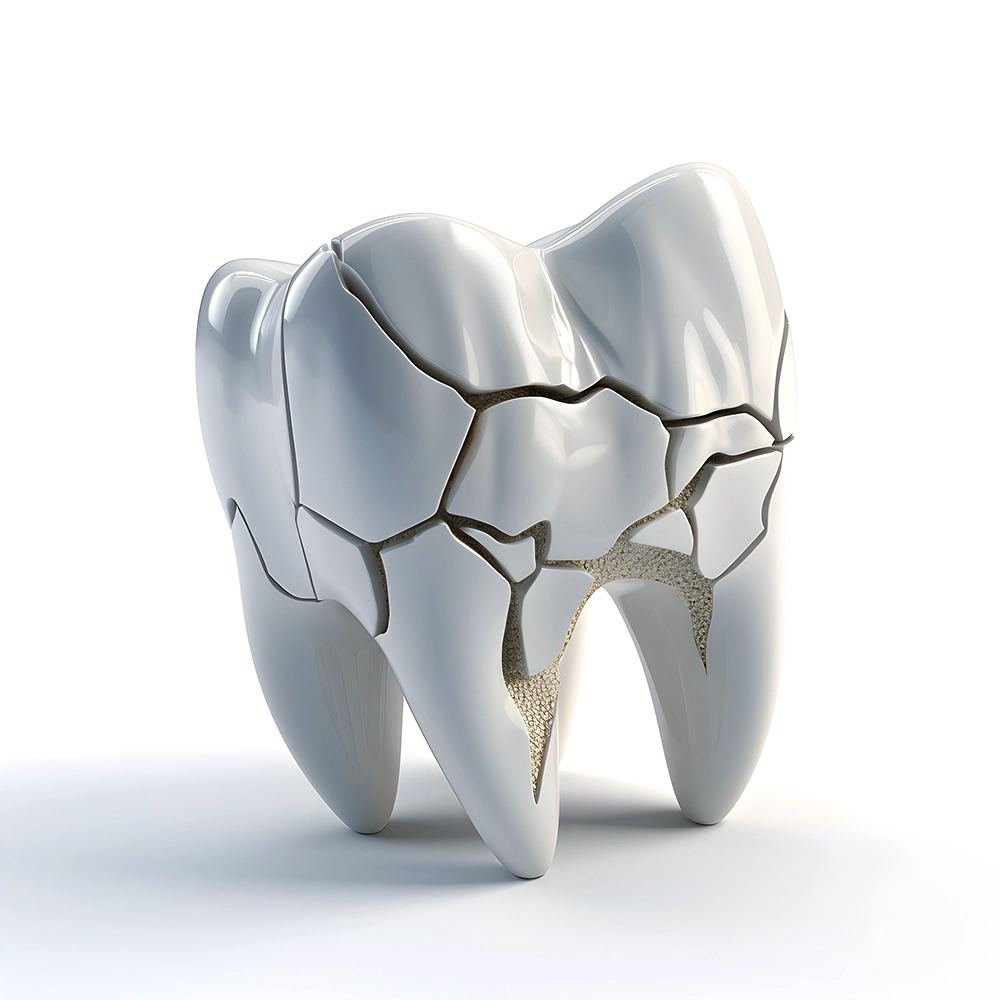

A highly detailed 3D rendering of a cracked tooth, depicting the intricate lines of a dental fracture, highlighting the urgency of dental intervention.

Accidental Tooth Loss or Damage:

Accidents happen quickly, whether from a fall, sports injury, or biting down on something hard. If a tooth is knocked out or damaged, quick action is vital to manage pain, control bleeding, and potentially save the tooth. Our experts are ready to help you through these urgent situations.